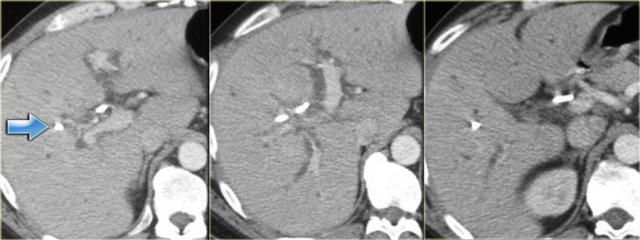

Late CT features are seen on the images on the left.

Study the images and then continue reading.

The findings are:

- Morphologic changes of cirrhosis (volume loss in the right lobe and a large caudate lobe (arrow)

- More pronounced dilatation of the bile ducts

Cholangiography is used in the initial diagnosis of the disease, when there are only subtle strictures and in patients known with PSC to look for new strictures that are suspicious for carcinoma.

On cholangiography we can see:

- Beading: alternating pattern of strictures and normal or slightly dilated ducts

- Pruned-tree: distal bile ducts are narrowed and difficult to see

- Mural irregularity: irregular luminal margin (best seen on the left in the extrahepatic duct)

- Diverticula: best seen in the next patient

On the left the typical findings in PSC.

Notice the diverticula on the image on the right.

Diverticula are very specific for the diagnosis PSC.

So when you see these diverticula, you should immediately search for subtle strictures in the intrahepatic ducts.